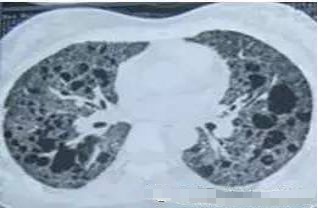

请问王大夫,这个那么像磨砂玻璃,这种是肺癌吗?

不是的,这个是肺泡蛋白沉积症,患者的肺像铺路石一样。